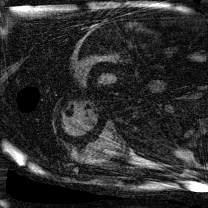

Supervised Deep-Learning (DL)-based reconstruction algorithms have shown state-of-the-art results for highly-undersampled dynamic Magnetic Resonance Imaging (MRI) reconstruction. However, the requirement of excessive high-quality ground-truth data hinders their applications due to the generalization problem. Recently, Implicit Neural Representation (INR) has appeared as a powerful DL-based tool for solving the inverse problem by characterizing the attributes of a signal as a continuous function of corresponding coordinates in an unsupervised manner. In this work, we proposed an INR-based method to improve dynamic MRI reconstruction from highly undersampled k-space data, which only takes spatiotemporal coordinates as inputs. Specifically, the proposed INR represents the dynamic MRI images as an implicit function and encodes them into neural networks. The weights of the network are learned from sparsely-acquired (k, t)-space data itself only, without external training datasets or prior images. Benefiting from the strong implicit continuity regularization of INR together with explicit regularization for low-rankness and sparsity, our proposed method outperforms the compared scan-specific methods at various acceleration factors. E.g., experiments on retrospective cardiac cine datasets show an improvement of 5.5 ~ 7.1 dB in PSNR for extremely high accelerations (up to 41.6-fold). The high-quality and inner continuity of the images provided by INR has great potential to further improve the spatiotemporal resolution of dynamic MRI, without the need of any training data.

翻译:在这项工作中,我们建议了一种基于IRI的方法,用这种方法来改进动态磁共振感应成像(MRI)重建,而该方法只是以高度低劣的 k-空间数据为基础,而该数据仅以磁共振坐标作为投入。具体地说,拟议的IRI将动态MRI图像作为一种隐含功能来表示,并将其编码到神经网络中。网络的权重仅从稀有的(k, t)空间数据本身中学习,而没有外部培训数据集或先前的图像。 利用基于IRI的强有力隐含性稳定化,同时不以清晰的动态和时空坐标坐标坐标坐标坐标作为投入。 拟议的IRIR将动态MRI图像作为一种隐含功能,将其编码到神经网络中。网络的权重仅从淡化的(k, t)空间数据本身学习,而没有外部培训数据集或先前的图像。